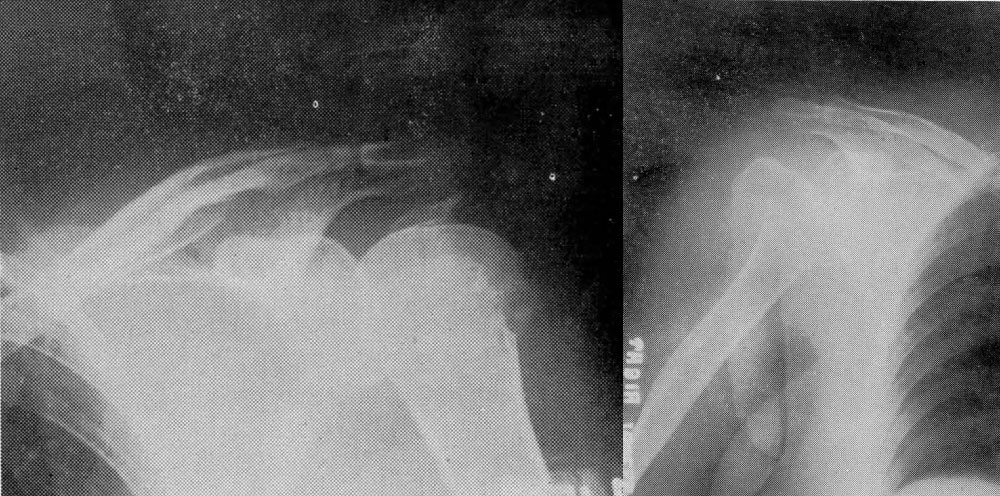

Roy Wert, MD, becomes chief of the department. Joint replacement procedures start becoming popularized around this time, and Dr. Wert develops a particular passion for this new treatment option.

Dr. Wert publishes a medical review on joint arthroplasty procedures for the shoulder, elbow, wrist, hand, hip, knee, and ankle.